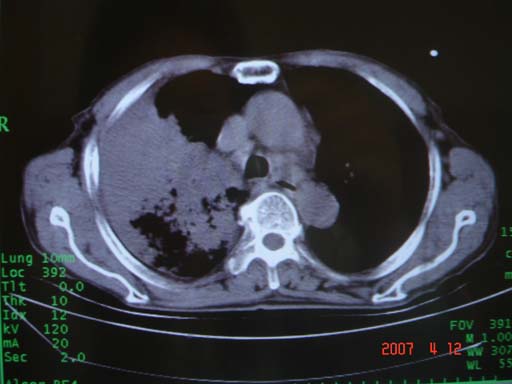

帮我 看看。男77岁咳嗽咯血2月发热2周!病人一般情况可 口痰为鲜红,有点象洗肉水(我看见他吐的痰了)

病灶局限在右肺中上叶,呈大片状实变影,内见空气支气管征,支气管分支较柔软,纵隔内未见肿大淋巴结.支持:感染性病变_1 大叶性肺炎.2 干酪性肺炎.

优先考虑右上肺干酪性肺炎并同侧中叶播散、胸腔积液。分析:右膈肌未见升高、纵隔未见明显右移,胸部各组淋巴结未见可疑肿大,中叶可见支气管铸形,肺野、肺门未见可确定肿块。

年龄偏大,应考虑右肺中央型肺癌并阻塞性肺炎 阻塞性肺不张,胸腔积液

考虑右侧中心型肺癌伴中叶肺不张,右侧 胸腔积液

右肺上叶中心型肺癌并上叶阻塞性肺炎,中叶炎症,右侧胸腔积液

右肺上叶后段支气管中断,首先考虑中央型肺癌并右肺不张及纵隔淋巴结转移,右侧胸腔积液。

右肺中心型肺癌可见支气管呈鼠尾状

有点象洗肉水的痰,其来源应当是实变引起的血细胞渗出导致,可见支气管气象,实变区有虫蚀状空洞,有明显胸腔积液,未见明显肺门区肿块影,考虑继发型肺结核,干酪性肺炎

右肺上叶实变,实变范围如此之大,如果用肺癌解释的化,应该是比较大的支气管开口发生完全阻塞,但观察上叶前后段支气管还是比较通畅,所以应考虑感染性病变,大叶性肺炎可能,建议抗炎治疗后复查。